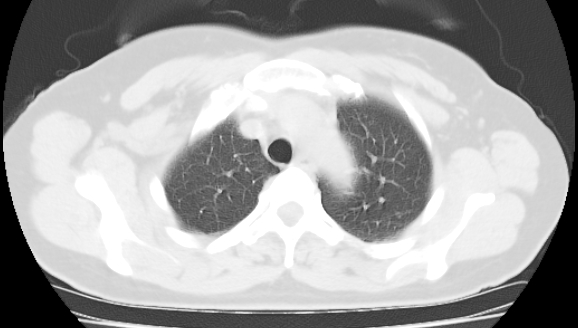

标题: CT25227:背部疼痛伴双侧胸壁痛2月,食欲差。 [打印本页]

标题: CT25227:背部疼痛伴双侧胸壁痛2月,食欲差。

肺结核并胸椎结核?请各位高手指教。

用椎体的条件来扫胸椎呀!考虑1左侧胸膜小结节形成2椎体结核并冷脓肿形成

左肺结核灶,胸椎结核并冷脓肿。

左肺结核灶,胸椎结核并冷脓肿